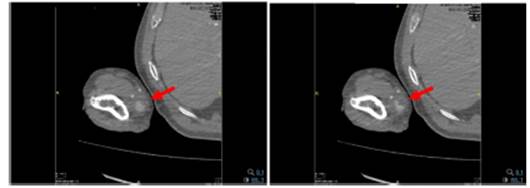

Acute lesion of the proximal right median nerve at the level of the elbow, of severe degree. Angio-CT

A pseudoaneurysm of the right ulnar artery measuring 22 x 21 mm in diameter, with a neck of 2 mm is observed (Fig. 2).